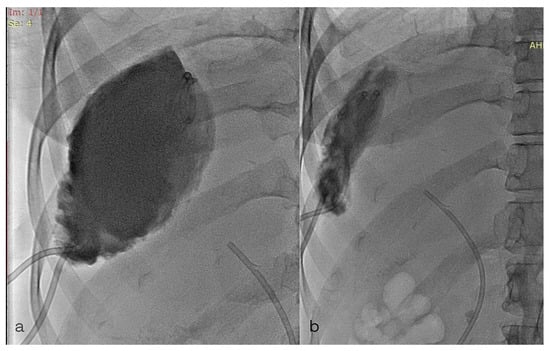

2. Case Report